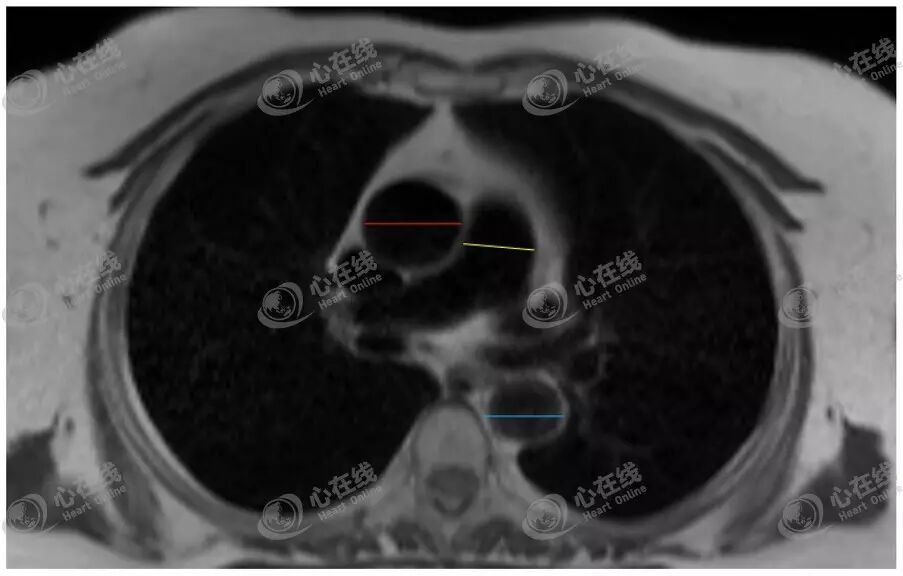

4、大血管径线测量

如图10,一般在HASTE横轴位图像的肺动脉平面上,测量肺动脉内径(黄色线所示)、升主动脉内径(红色线所示)及降主动脉内径(蓝色线所示)。

图10